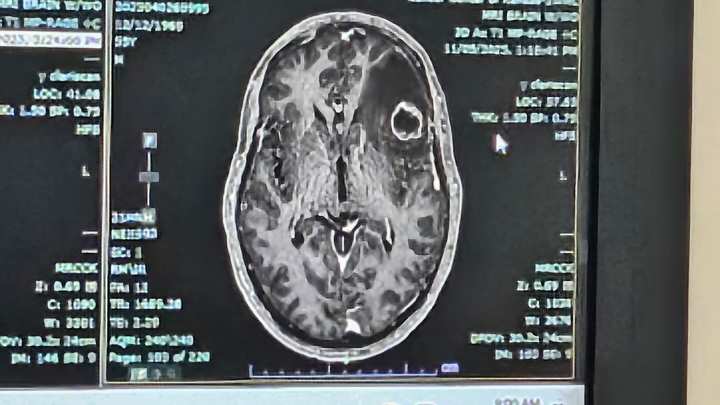

My father was diagnosed with cancer in March 2024. He has had a massive tumor on his left lung, pressing into nerves causing nerve damage and multiple brain tumors. We found out 4 weeks ago that he has a new tumor on his brain twice as big as his first one, causing swelling and memory loss.